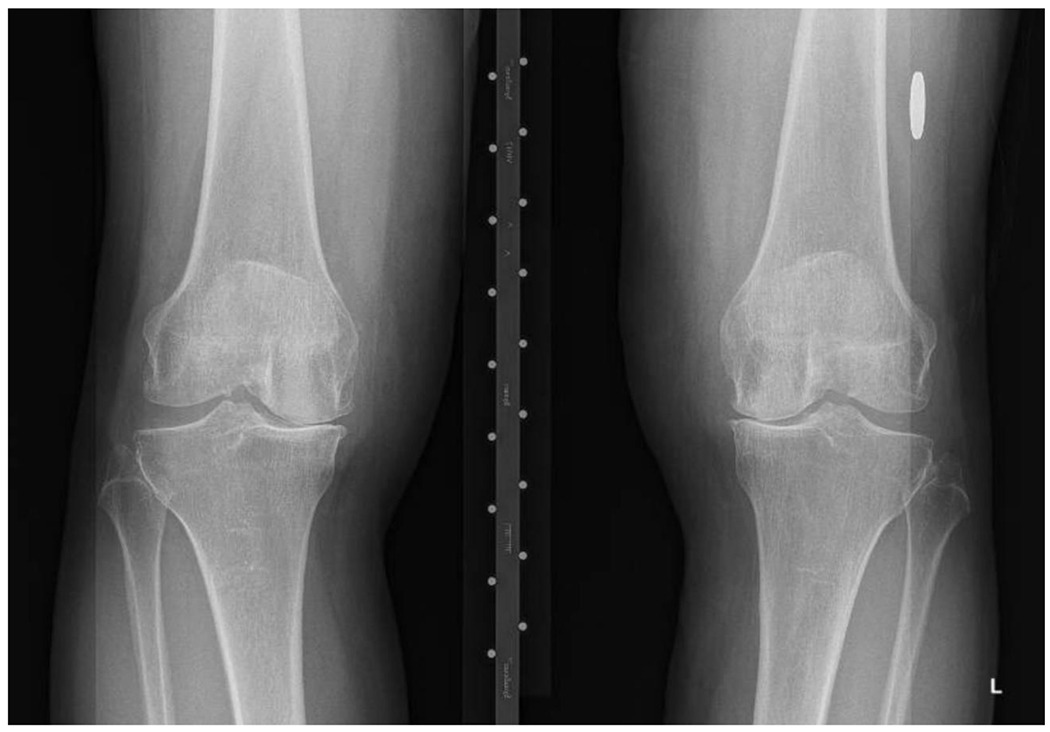

OA arises from complex biological processes that include cartilage, bone, synovium, ligaments, periarticular fat, meniscus, and muscle.15 The classic features of OA noted on radiographs include joint space narrowing due to loss of articular cartilage and meniscus, and bony changes including sclerosis of subchondral bone and osteophytes (Figure 1A). The effects of OA on cartilage, meniscus, syovium, subchondral bone and other structures can be appreciated on magnetic resonance imaging (Figure 1B).

방사선 사진에서 관찰되는 OA의 전형적인 특징으로는

관절 연골과 반월판의 손실로 인한 관절 공간 협착과

연골 하골 및 골육종의 경화증을 포함한 뼈의 변화가 있습니다(그림 1A).

Figure 1A:

Bilateral varus deformity with medial joint space narrowing (nearly bone on bone) and osteophyte formation. Thin arrows show joint space narrowing and thick arrows medial marginal osteophytes.

내측 관절 공간이 좁아지고(거의 뼈와 뼈가 맞닿음) 골육종이 형성된 양측 내반 변형입니다.

가는 화살표는 관절 공간 협착을, 굵은 화살표는 내측 가장자리 골극을 나타냅니다.

These data suggest a presumptive diagnosis of hip or knee OA can be made on the basis of the history and physical exam. Radiographs portray the severity of structural damage and improve specificity when osteophytes or joint space narrowing are present. Pathologic features and symptoms of OA can occur before osteophytes are present on radiographs. Thus, a normal radiograph does not exclude OA. If the clinical presentation is highly suggestive of OA, clinicians should initiate management (detailed below) despite normal radiographs. Knee radiographs should be performed with the patient standing to reveal the extent of joint space narrowing of the tibiofemoral joint. For research purposes, hip and knee radiographs are typically assessed with the Kellgren-Lawrence grading system, with grade 0 representing no pathologic findings; Grade 1 questionable osteophytes; Grade 2 definite osteophytes; Grade 3, definite joint space narrowing; and Grade 4 advanced joint space narrowing.33,34 The radiograph in Figure 1A is Kellgren-Lawrence Grade 3 and nearly K-L 4 because of the advanced medial joint space narrowing is nearly bone-on-bone.